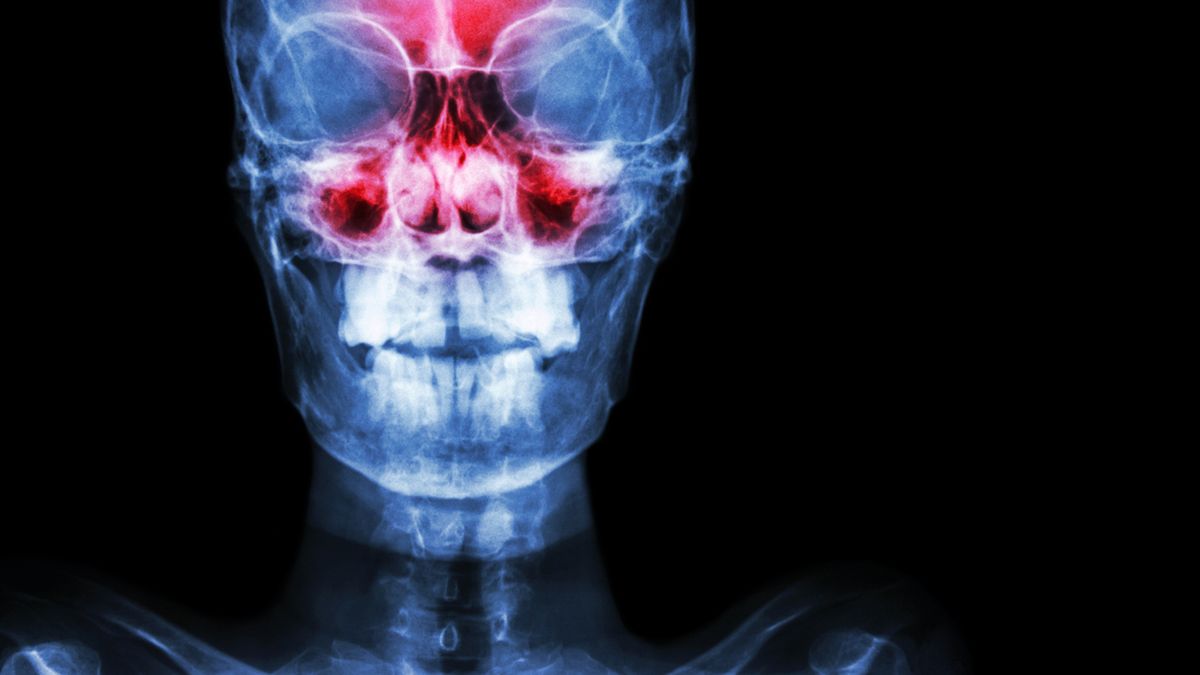

To dzięki zatokom nasza czaszka jest lekka i odporna na urazy. Chronią one mózg, biorąc czynny udział w wymianie gazowej. Nawilżają i ogrzewają powietrze wdychane przez nos. Zatoki wytwarzają też rezonans dźwiękowy i modulujący, który wzmacnia dźwięki głosowe.

Chore zatoki to problem nasilający się sezonowo. Jest obecnie jedną z dziesięciu najczęściej pojawiających się dolegliwości zdrowotnych. Cierpią wszyscy bez względu na wiek i płeć.

Nieleczone zapalenia zatok prowadzą do licznych komplikacji. Jakich? To np. zaburzenia węchu, bóle głowy, powikłania oczodołowe i oczne, zapalenia kości twarzoczaszki oraz powikłania wewnątrzczaszkowe. Chorzy skarżą się też na ogólny spadek odporności i wydolności organizmu.